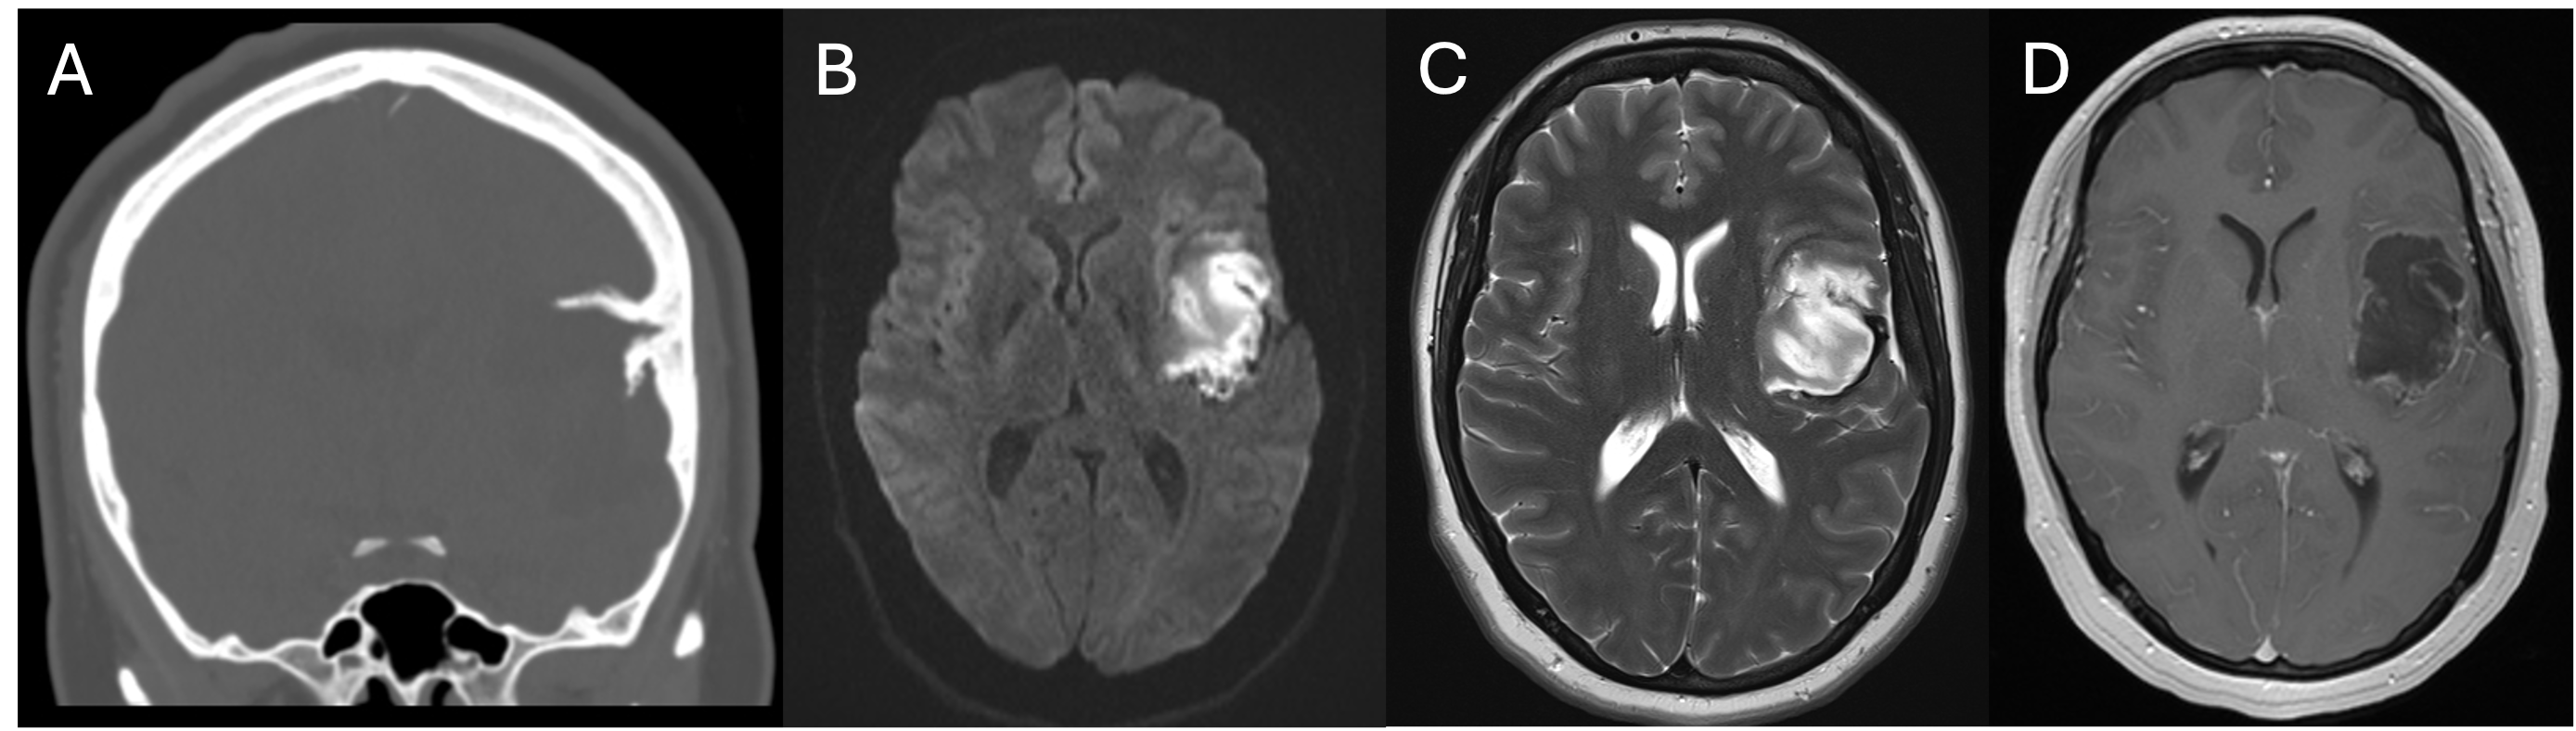

Results:

A 67-year old woman with chronic hypertension, hyperlipidemia and diabetes mellitus non-compliant to medication presented with a 10-day history of recurrent visual phenomena in the left visual field. She described stationery multi-coloured flashing lights which decreased in intensity, brightness and size after 3 minutes. She was alert and conscious during attacks. There was no limb jerking. Neurological examination was normal with no visual field defect. Capillary glucose was 28.1 mmol/L, Hba1c 9% and B-hydroxybutyrate < 0.1. She was treated with actrapid 8 units, glipizide 5 mg BD and empagliflozin 12.5 mg OM. Interictal electroencephalogram was normal with no epileptiform activity. Brain magnetic resonance imaging revealed restricted diffusion in the right occipital cortex with corresponding cortical thickening and increased FLAIR signal with subtle hypodensity on GRE sequence. Her visual symptoms improved dramatically with hydration and diabetic control. She was treated with a short course of keppra. One month later repeat MRI brain showed resolution of the DWI and FLAIR abnormalities.

Conclusions:

Visual hallucinations are an uncommon but well recognised and fully reversible complication of HHS. Clinicians should not forget HHS in the workup of occipital lobe.

Initial dwi